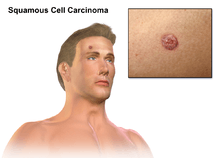

Squamous cell carcinoma

| SCC of the skin tends to arise from pre-malignant lesions, actinic keratoses; surface is usually scaly and often ulcerates (as shown here). | |

Squamous cell carcinoma (SCC or SqCC), also known as squamous cell cancer, is cancer that begins from squamous cells, a type of skin cell.[1] It is one of the main types of skin cancer. Cancers that involve the anus, cervix, head and neck, and vagina are also most often squamous cell cancers.[1] The esophagus, urinary bladder, prostate, and lung are other possible sites.

SCC of the skin begins as a small nodule and as it enlarges the center becomes necrotic and sloughs and the nodule turns into an ulcer.

- The lesion caused by SCC is often asymptomatic

- Ulcer or reddish skin plaque that is slow growing

- Intermittent bleeding from the tumor, especially on the lip

- The clinical appearance is highly variable

- Usually the tumor presents as an ulcerated lesion with hard, raised edges

- The tumor may be in the form of a hard plaque or a papule, often with an opalescent quality, with tiny blood vessels

- The tumor can lie below the level of the surrounding skin, and eventually ulcerates and invades the underlying tissue

- The tumor commonly presents on sun-exposed areas (e.g. back of the hand, scalp, lip, and superior surface of pinna)

- On the lip, the tumor forms a small ulcer, which fails to heal and bleeds intermittently

- Evidence of chronic skin photodamage, such as multiple actinic keratoses (solar keratoses)

- The tumor grows relatively slowly